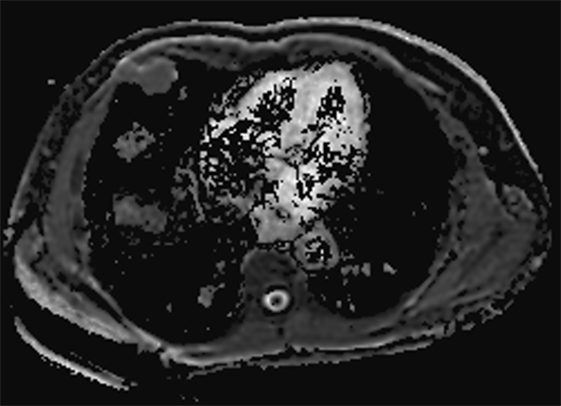

A 60-year-old Hispanic male presented to his primary care physician office with an asymptomatic, but palpable right anterior chest wall mass. The patient has no significant past medical history except for a clavicular fracture sustained during soccer. Physical examination revealed an asymptomatic 4 cm soft tissue palpable mass of the right anterior chest wall. The skin was intact, no erosive markings were present. The patient’s laboratory work up was unremarkable. Radiology work up included CT chest, MRI of the chest and PET/CT. His CT chest axial series on bone windows demonstrated a 2.8 × 3.8 × 2.9 cm pleural based soft tissue mass eroding through the right anterior fifth rib (Figure 1). There was mild compression of the nearby lung parenchyma, however no pulmonary lesions were identified. Further characterization of the mass by MRI contrast enhanced images of the chest revealed a well-circumscribed pleural based T1 hypo-intense avidly enhancing soft tissue mass in the right anterior chest wall involving the right anterior fifth rib and into the overlying sub-pectoral soft tissues (Figure 2). The mass also demonstrated restricted diffusion which is indicative of high cellularity (Figure 3 and Figure 4). PET/CT imaging revealed mild hypermetabolic activity of the mass with maximum SUV of 1.9 (Figure 5).

Figure 4. Apparent diffusion imaging correlate with hypointense signal of the mass.